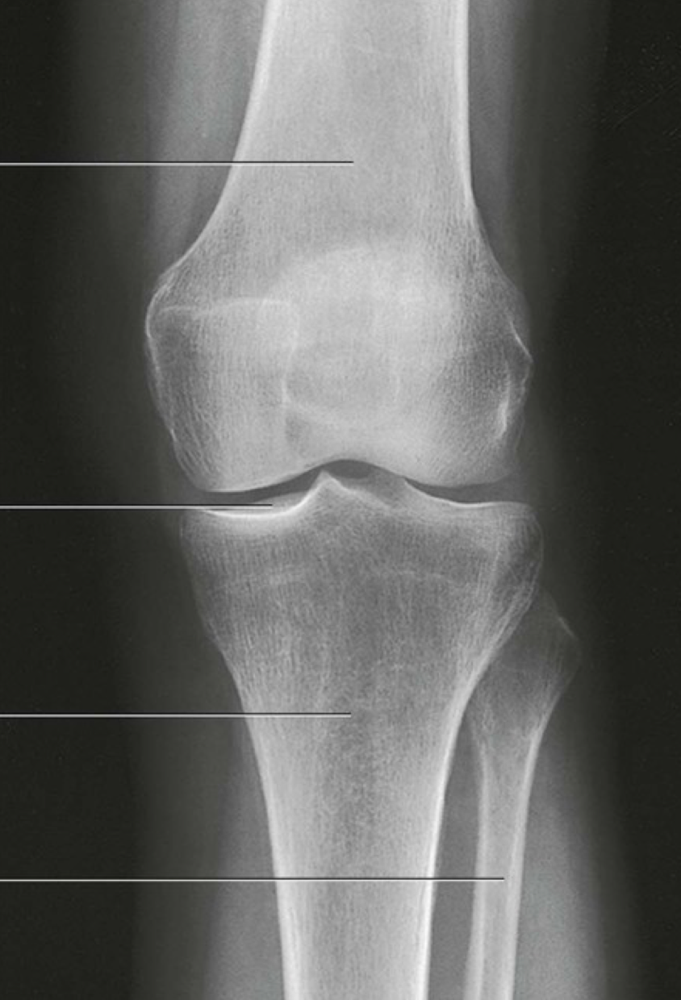

Question 6

Question

Label the image

Image:

de7d08d4-6109-4960-80bc-7c5ca5e03e59 (image/png)

Answer

femur

patella

medial femoral condyle

lateral femoral condyle

lateral tibial plateau

medial tibial plateau

medial tibial condyle

fibula

tibia